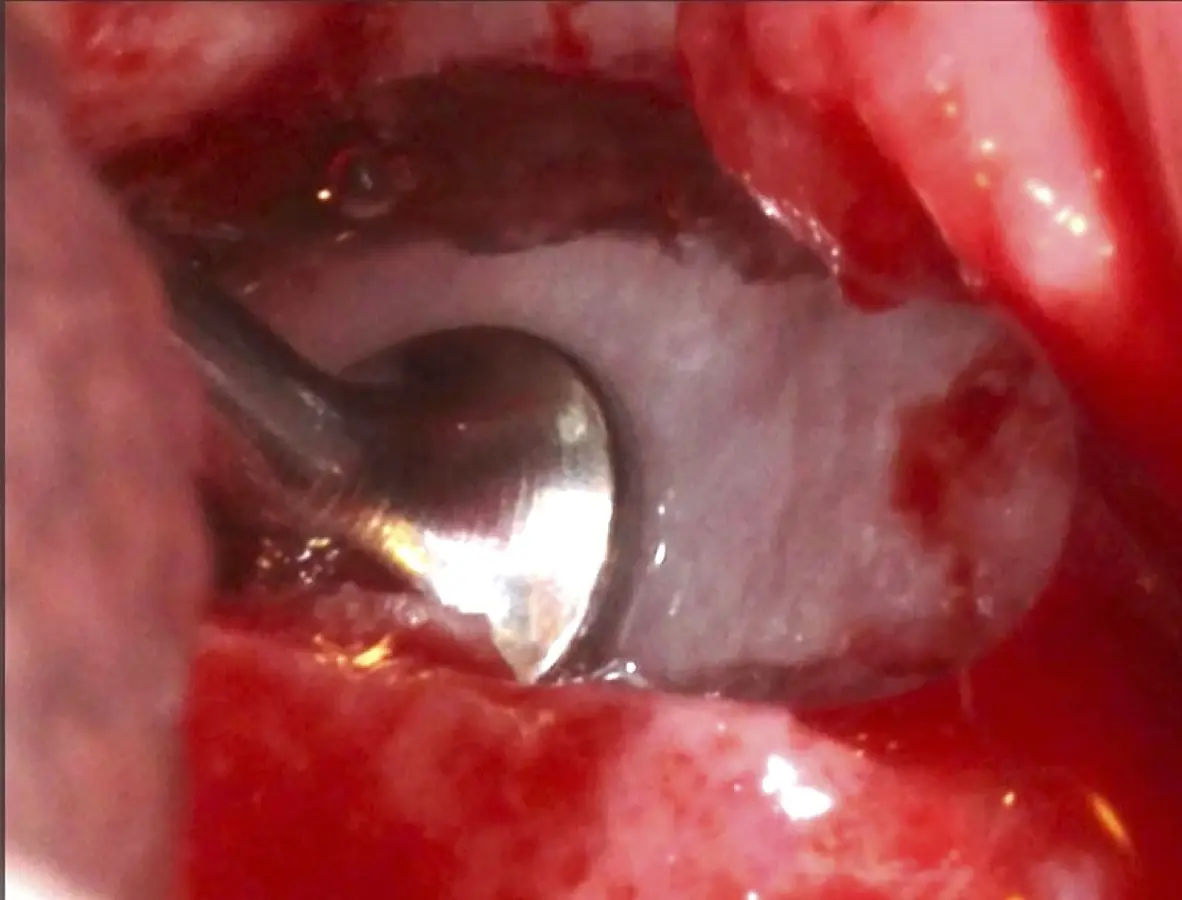

Inserto de presión hidráulica iniciando el desprendimiento de la membrana de Schneider (a, b ).

Figura 7. Inserto de presión hidráulica iniciando el desprendimiento de la membrana de Schneider (a, b ).

Figura 17. Inicio del desprendimiento de la membrana de Schneider con el inserto de presión hidráulica.

Figura 25. Introducción del bloque óseo de la pared lateral dentro del seno maxilar: inicio del desprendimiento de la membrana con el inserto de presión hidráulica.